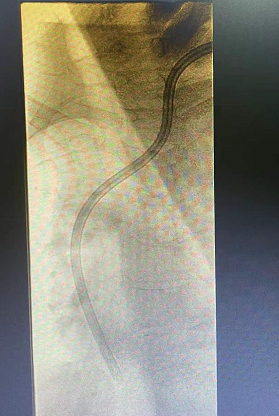

王女士,确诊尿毒症7+年时间,长期依靠左侧cuff导管行血液透析治疗,因确诊导管感染,经过反复治疗后效果不佳,所以必须拔除维持患者生命的唯一的血管通路,但是血管通路是尿毒症患者维持生存的必备条件,目前患者又处于病危状态、高钾、水负荷重,心衰明显,必须立即建立新的血管通路行血液透析治疗去维持生命,由于患者自身血管条件差,动静脉内瘘建立困难,临时血管通路建立难度极大,临时安置股静脉导管、颈内静脉导管均失败,不能满足血液透析要求,对此,患者悲痛欲绝、陷入绝望,家属也不放弃任何能够救治的机会,啃啃哀求郑医生能够为患者开辟一条“活路”;于是肾病科主任毕伟红、副主任王婷立刻紧急召开血管通路小组会议,由于王女士基础疾病多且复杂,DSA下造影显示左侧头臂静脉重度狭窄伴血栓形成,手术难度及风险极大,经过讨论,主刀医生郑星和张艳玲医生快速为患者量身定制手术方案,决定联合运用介入技术(DSA)+PTA技术,为王女士开辟一条新的“活路”。王女士,确诊尿毒症7+年时间,长期依靠左侧cuff导管行血液透析治疗,因确诊导管感染,经过反复治疗后效果不佳,所以必须拔除维持患者生命的唯一的血管通路,但是血管通路是尿毒症患者维持生存的必备条件,目前患者又处于病危状态、高钾、水负荷重,心衰明显,必须立即建立新的血管通路行血液透析治疗去维持生命,由于患者自身血管条件差,动静脉内瘘建立困难,临时血管通路建立难度极大,临时安置股静脉导管、颈内静脉导管均失败,不能满足血液透析要求,对此,患者悲痛欲绝、陷入绝望,家属也不放弃任何能够救治的机会,啃啃哀求郑医生能够为患者开辟一条“活路”;于是肾病科主任毕伟红、副主任王婷立刻紧急召开血管通路小组会议,由于王女士基础疾病多且复杂,DSA下造影显示左侧头臂静脉重度狭窄伴血栓形成,手术难度及风险极大,经过讨论,主刀医生郑星和张艳玲医生快速为患者量身定制手术方案,决定联合运用介入技术(DSA)+PTA技术,为王女士开辟一条新的“活路”。王女士,确诊尿毒症7+年时间,长期依靠左侧cuff导管行血液透析治疗,因确诊导管感染,经过反复治疗后效果不佳,所以必须拔除维持患者生命的唯一的血管通路,但是血管通路是尿毒症患者维持生存的必备条件,目前患者又处于病危状态、高钾、水负荷重,心衰明显,必须立即建立新的血管通路行血液透析治疗去维持生命,由于患者自身血管条件差,动静脉内瘘建立困难,临时血管通路建立难度极大,临时安置股静脉导管、颈内静脉导管均失败,不能满足血液透析要求,对此,患者悲痛欲绝、陷入绝望,家属也不放弃任何能够救治的机会,啃啃哀求郑医生能够为患者开辟一条“活路”;于是肾病科主任毕伟红、副主任王婷立刻紧急召开血管通路小组会议,由于王女士基础疾病多且复杂,DSA下造影显示左侧头臂静脉重度狭窄伴血栓形成,手术难度及风险极大,经过讨论,主刀医生郑星和张艳玲医生快速为患者量身定制手术方案,决定联合运用介入技术(DSA)+PTA技术,为王女士开辟一条新的“活路”。郑星医生表示在:介入技术能够快速发现患者血管通路问题所在,能让“隐形”的血管可视化,精准定位,提高手术操作成功率;由于王女士左侧头臂静脉重度狭窄伴血栓形成,导管通过狭窄部位困难,然而利用PTA技术能够扩张血管重度狭窄部位,让导管顺利通过,两种技术联合运用,极大地降低手术风险,减少了患者的痛苦。生命线的顺利重置,血液透析治疗的顺利开展,让患者及家属顿时喜笑颜开,重燃了患者生存的希望。

(术前) (术前) (术后)

介入技术(DSA):指通过在血管中注入造影剂,使血管显影,根据血管的分布、形态、位置等变化来判断病变的具体部位、范围及程度,并可经导管行介入治疗。

经皮血管腔内血管成形术(PTA):通过经皮穿刺血管,置入导丝,沿导丝将球囊输送至血管狭窄病变处,将扩张球囊送入血管狭窄部位并对其进行扩张,从而将狭窄血管矫正至正常血管内径。